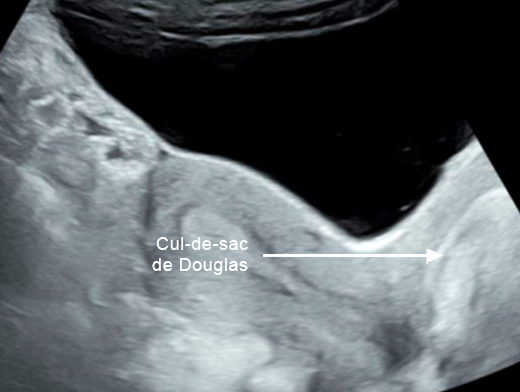

Concernant l’hématome sous-capsulaire du foie : Tableau 3 (Rodolphe Matias de Sousa, La Revue du Praticien) Concernant l’échographie transabdominale à la recherche d’un hémopéritoine :on regarde deux espaces, le cul-de-sac de Douglas entre l’utérus et le rectum, et l’espace de Morrison entre le foie et le rein. Figure 3a (Rodolphe Matias de Sousa, La Revue du Praticien)Figure 3b (Rodolphe Matias de Sousa, La Revue du Praticien)Figure 3c (Rodolphe Matias de Sousa, La Revue du Praticien) Pour rappel, concernant l’échographie en gynécologie : Figure 4a (Rodolphe Matias de Sousa, La Revue du Praticien)Figure 4b (Rodolphe Matias de Sousa, La Revue du Praticien)Figure 4c (Rodolphe Matias de Sousa, La Revue du Praticien)Figure 4d (Rodolphe Matias de Sousa, La Revue du Praticien)Figure 4e (Rodolphe Matias de Sousa, La Revue du Praticien)Figure 4f (Rodolphe Matias de Sousa, La Revue du Praticien)Figure 4g (Rodolphe Matias de Sousa, La Revue du Praticien)Figure 4h (Rodolphe Matias de Sousa, La Revue du Praticien)Figure 4i (Rodolphe Matias de Sousa, La Revue du Praticien)